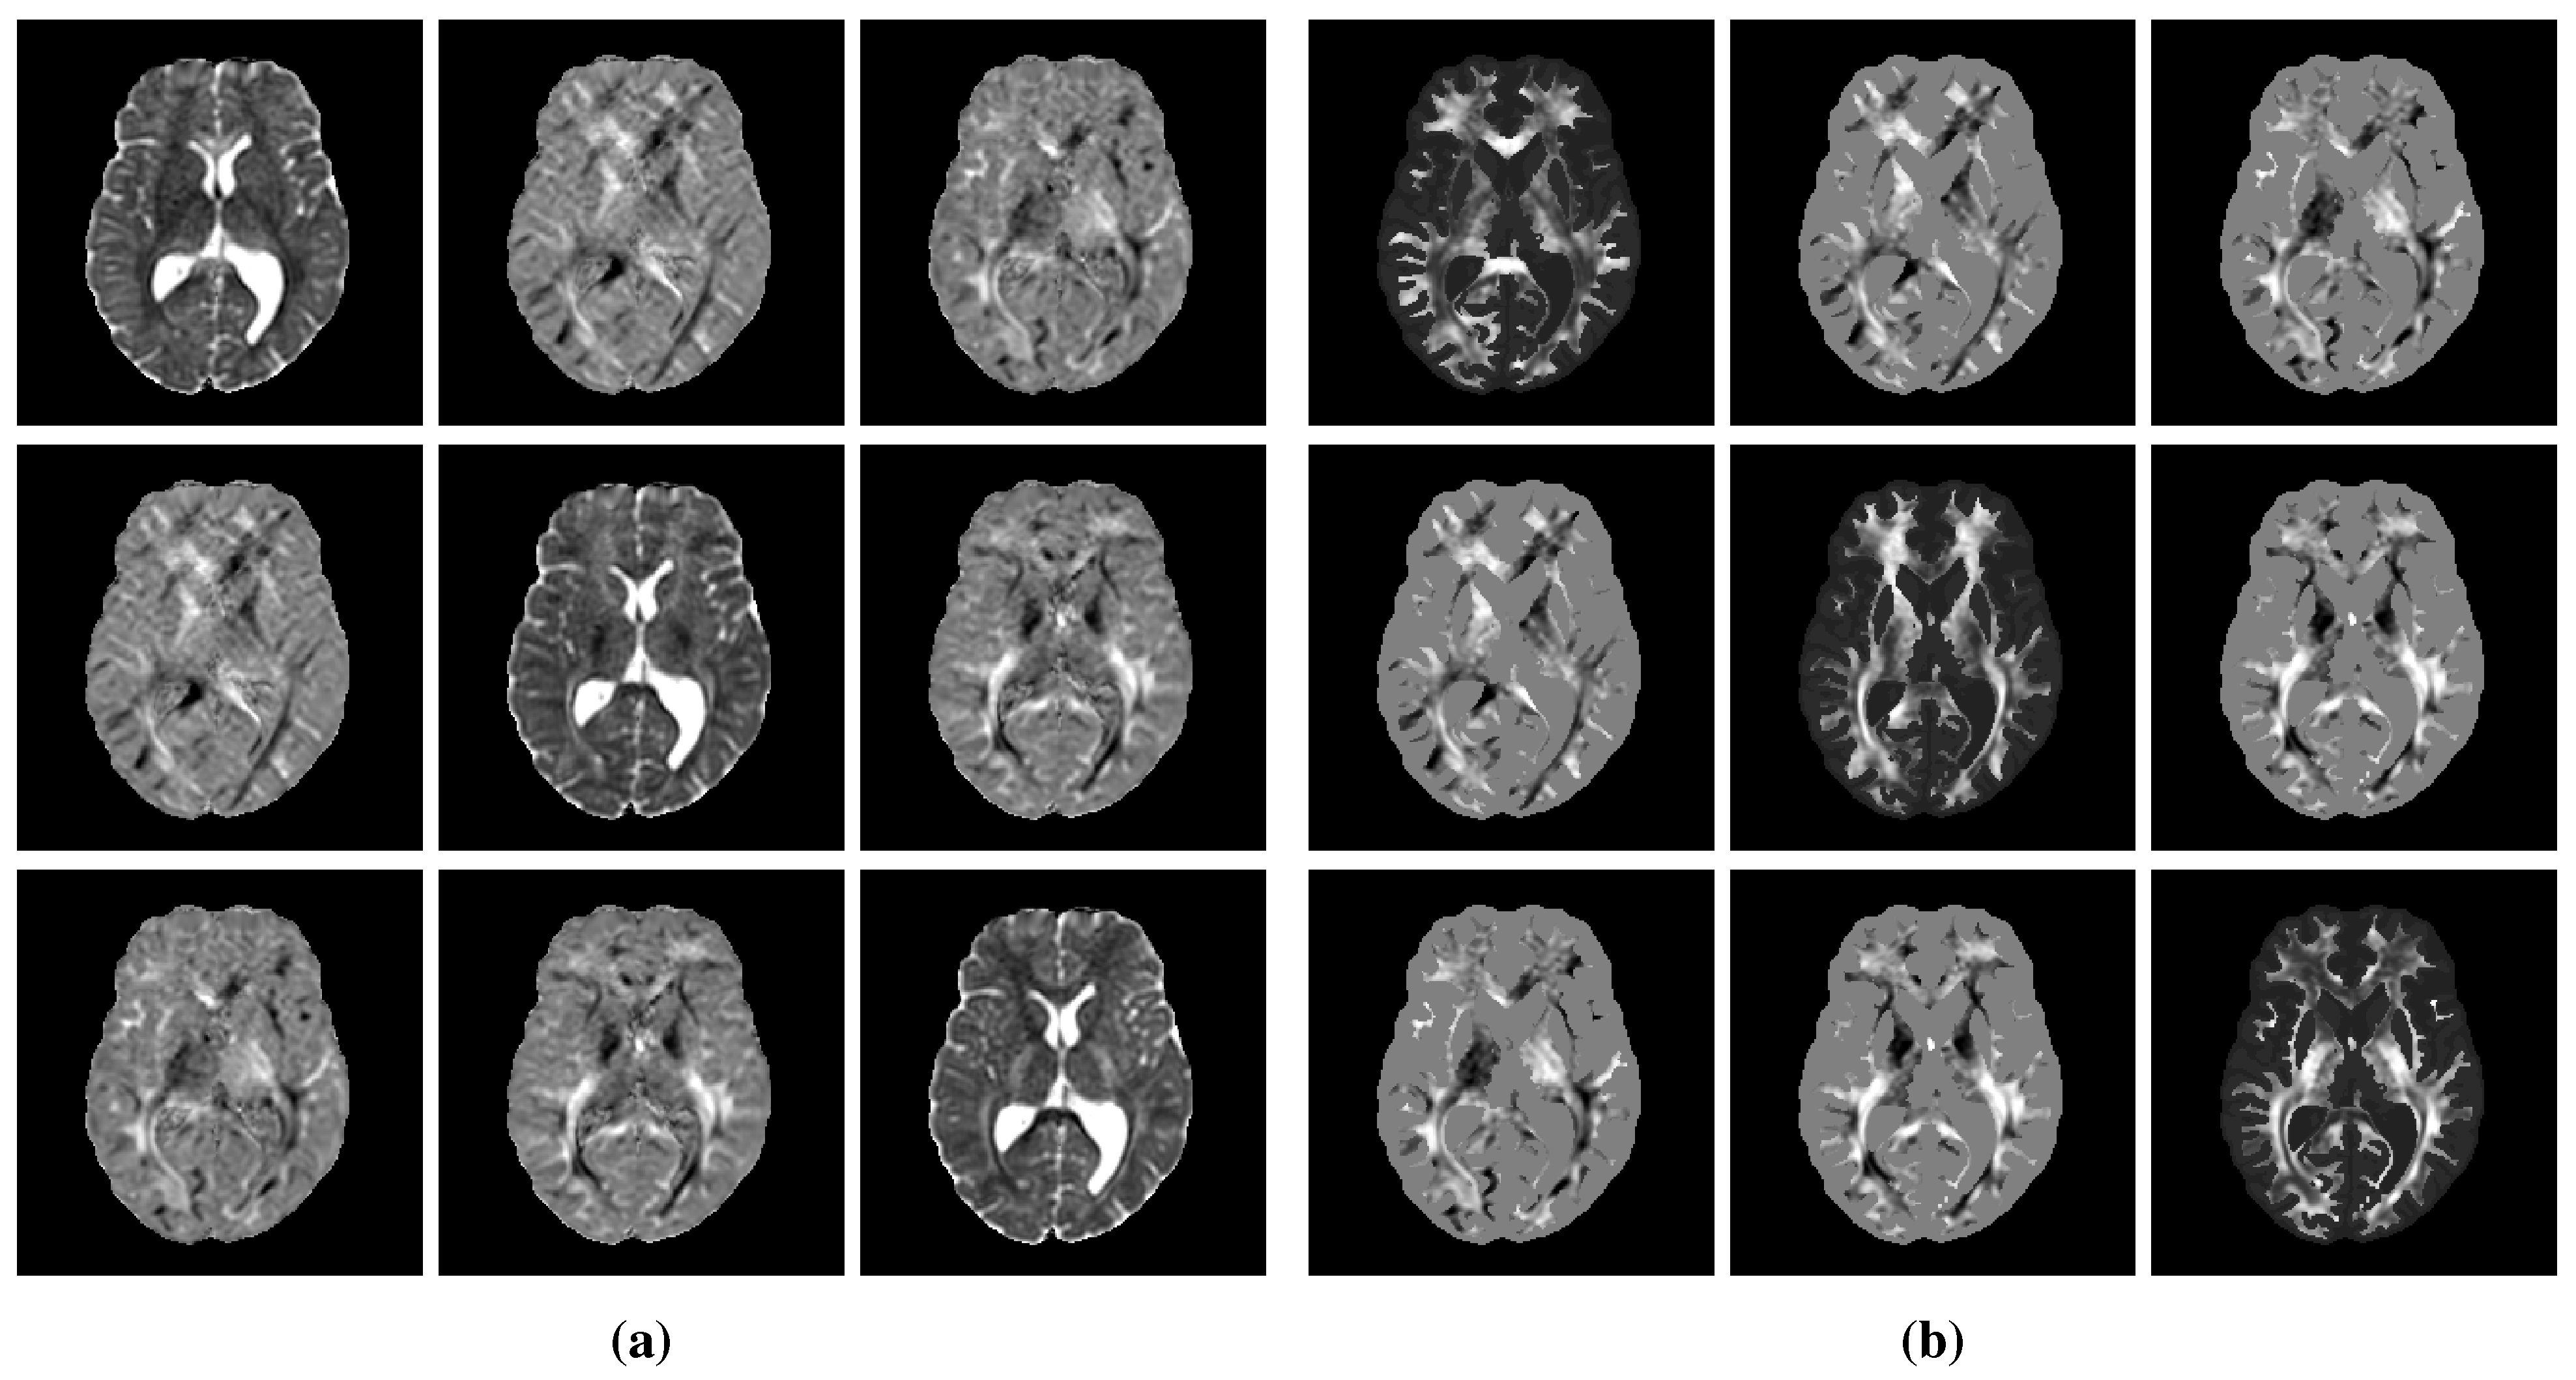

The extracted brain domain was further segmented on the registered T1 BRAVO image into white matter, gray matter, and cerebrospinal fluid using an in-house implementation of the MICO intensity-based clustering algorithm comprising a bias field correction step [38]. Manual corrections were further applied to the mis-segmented basal nuclei and falx cerebri. This last step is crucial to prevent the migration of tumor cells between brain hemispheres via routes other than the corpus callosum, as highlighted previously [2]. The segmentation results were finally merged into a single brain map. An example of T2 FLAIR and T1 BRAVO images with the corresponding brain mask and segmented brain map is depicted in Figure 1.

For reasons that will become clearer in Section 2.4, a unit tumor cell diffusion tensor was built at this stage by fixing d white to 1. A value of 0.1 was chosen for the d gray / d white ratio, as proposed previously in [13] to account for the restricted migration of tumor cells in gray compared to white matter. This ratio was supposed constant among all subjects as it is expected to depend exclusively on the structural organization of healthy white versus gray matter and not on the tumor characteristics. Similarly, the anisotropy factor a was fixed to 10 for all subjects, as suggested in [14]. An example of processed DTI data is depicted in Figure 2. The processed MR data of the 6 volunteers used in this study are publicly available at https://doi.org/10.5281/zenodo.6563613 (accessed on 17 May 2022). Further details on these data are available in Appendix B.

For each synthetic tumor, a tumor cell diffusion tensor field D ( x ) was then obtained by multiplying the unit (unscaled) diffusion tensor derived as described in Section 2.3.6 by the derived value of d white . As a reminder, the ratio d gray / d white was considered constant among tumors in this work (see Section 2.3.6). A tumor was finally grown from the sampled seed, tumor cell diffusion tensor field D ( x ) , and proliferation rate ρ using the model and the simulated tumor cell distributions at times t 1 4 were stored. Examples of synthetic tumors are depicted in Figure 4. The corresponding model parameter values are provided in Table 2.

Figure A1. Example of true (1st row) and estimated (2nd row) three-dimensional tumor cell-density distributions at times t 2 4 (1st to 3rd column, axial slices) along with the corresponding absolute error maps (3rd row) for a test tumor ( d = 46.20   mm 2 year 1 , ρ = 12.92   year 1 , t 1 = 130   d , t 2 = 268   d ). The imaging contours for threshold values c 1 = 0.80 and c 2 = 0.16 superimposed to the T1 and T2 FLAIR image are depicted in the 4th and 5th rows, respectively. The blue, red, and green segments respectively correspond to the target, prediction, and overlapping contour voxels. MAE: mean absolute error for c > 0.01 , d H : Hausdorff distance, d S : average symmetric surface distance.

Figure A2. Example of true (1st row) and estimated (2nd row) three-dimensional tumor cell-density distributions at times t 2 4 (1st to 3rd column, axial slices) along with the corresponding absolute error maps (3rd row) for a test tumor ( d = 9.52   mm 2 year 1 , ρ = 25.77   year 1 , t 1 = 94   d , t 2 = 225   d ). The imaging contours for threshold values c 1 = 0.80 and c 2 = 0.16 superimposed to the T1 and T2 FLAIR image are depicted in the 4th and 5th rows, respectively. The blue, red, and green segments correspond to the target, prediction, and overlapping contour voxels, respectively. MAE: mean absolute error for c > 0.01 , d H : Hausdorff distance, d S : average symmetric surface distance.